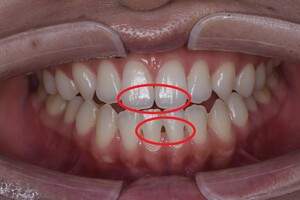

プロフェショナルクリーニング(PMTC)

治療前

治療後

| 年齢 | 26歳・女性 |

| 主訴 | 主訴:着色除去 治療部位:全顎 |

| 治療内容 | PMTC(自費診療) |

| 治療期間 | 30分 |

| 費用 | 5,500円 (2023年5月現在) |

| リスク・副作用 | ・生活習慣(喫煙・コーヒーなど)により再度着色することがあります。 ・PMTCは歯を白くするものではなく着色・バイオフィルムの除去を目的としています。 ・保険適用外の施術です。 |

| 治療方針 | プロフェショナルクリーニング(PMTC)後ホワイトニングを行う予定です。 |

| 特記事項 | 右下3番、2番の間に着色が目立ち、歯ブラシの動かし方の確認を行うとストロークが大きく、着色部位に歯ブラシが当たっていませんでした。歯ブラシが歯面に当たる角度を確認し、細かく振動を送るように動かすよう指導しました。一緒にステイン除去効果のある歯磨剤のおすすめを行いました。 |

| 担当者所見 | 右下3番、2番の間の着色が気になると来院されPMTCを行いました。喫煙の習慣はなく日常的にコーヒーを飲んでいるとのことでした。クリーニング後は歯がツルツルになったと喜んでくださいました。 |